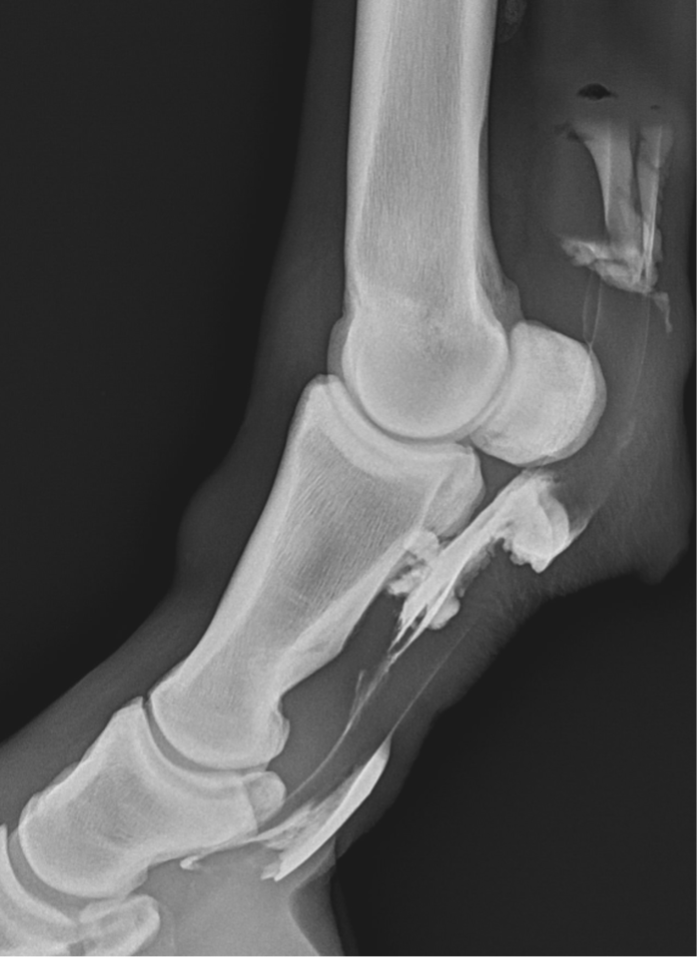

Upon further examination, contrast radiographs and ultrasound scans failed to identify any significant abnormalities apart from swollen synovium within the DFTS. To address this issue, our veterinary team administered 5mg of triamcinolone acetonide along with 20mg of HA, complemented by a compression wrap. Subsequently, the horse underwent a two-week confinement period in a small yard, followed by gradual reintroduction to exercise through 10 minutes of hand walking twice daily, with the distal limb wrapped for additional support.